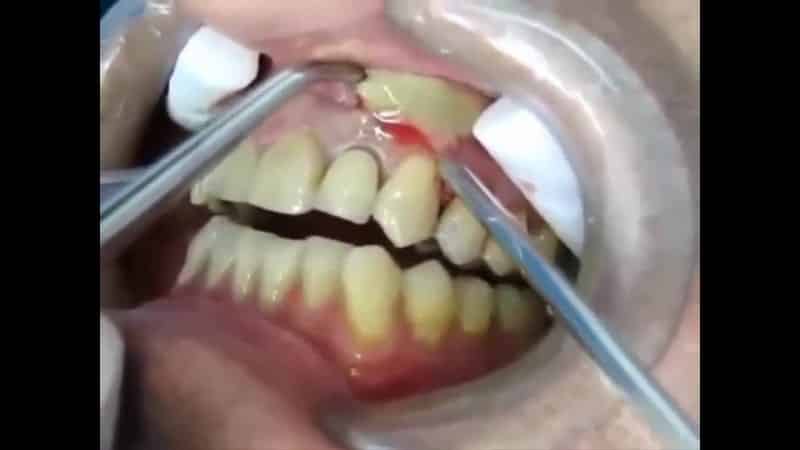

В процессе формирования волдырей и свищей часто возникает пульсирующая боль. После того как гнойный канал прорывается, болевые ощущения уменьшаются вместе с отечностью. Лечение включает в себя дезинфекцию инфекционного очага и пломбирование каналов, пораженных кариесом внутри зуба. Свищевой канал вскрывается при наличии высокой температуры, болей, отечности и гнойного содержимого в десне. Перед началом процедуры выполняется рентгенография для выявления кистозных или гранулемных образований.

Лечебные мероприятия направлены на обеспечение оттока жидкости от гранулемы, либо удаление кисты с последующим пломбированием зуба. Внешнее образование вскрывается с наружной стороны десны, а внутреннее – изнутри. Возможно распломбирование зуба или сверление канала для обеспечения гнойного оттока. В некоторых случаях может потребоваться удаление зуба для качественного лечения. После вскрытия свища открытую рану оставляют, периодически дезинфицируя ее с помощью полоскания, что способствует быстрому удалению скопившейся жидкости, а также физиотерапевтическими процедурами, направленными на лечение воспаления.

Очистка от микробов осуществляется с дополнительными методами, такими как промывание свищевого канала антисептическим раствором или применение антибактериальных паст и гелей. Врачи могут назначить противовирусные и противовоспалительные препараты, а иногда и антибиотики. После исчезновения симптомов, отечности и покраснения, очаг постепенно заживает, и в дальнейшем устанавливается временная пломба в зубной канал. Через десять дней, при отсутствии признаков инфекции, ставится постоянная пломба.